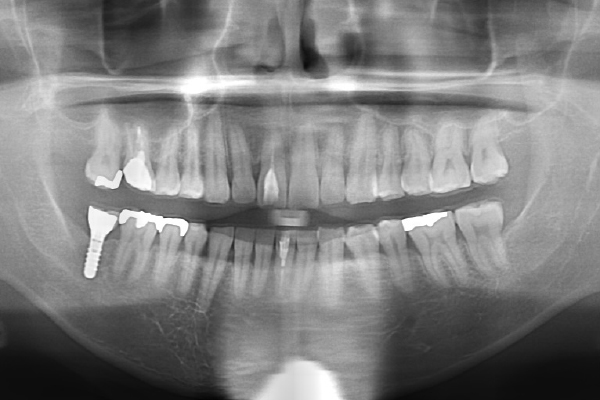

インプラントの症例

Case1 【30代男性】

- 右側下顎第二大臼歯部にインプラント治療

Before

| 主訴 | 奥歯で噛めるようになりたい |

|---|---|

| 治療期間 | 3ヶ月 |

| 治療費 | ¥440,000(税込) |

| 治療のリスク | 疼痛、腫脹など |